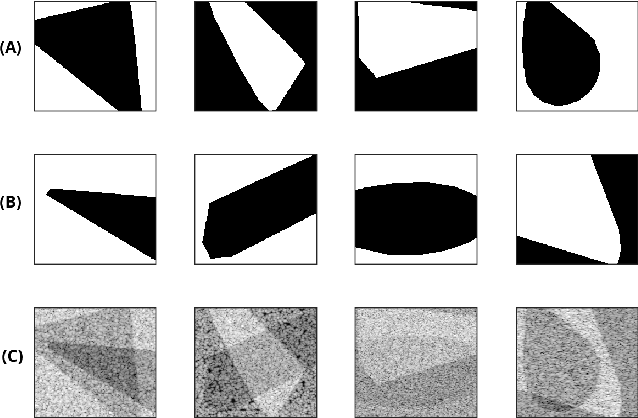

Abstract:Quantitative Ultrasound (QUS) provides important information about the tissue properties. QUS parametric image can be formed by dividing the envelope data into small overlapping patches and computing different speckle statistics such as parameters of the Nakagami and Homodyned K-distributions (HK-distribution). The calculated QUS parametric images can be erroneous since only a few independent samples are available inside the patches. Another challenge is that the envelope samples inside the patch are assumed to come from the same distribution, an assumption that is often violated given that the tissue is usually not homogenous. In this paper, we propose a method based on Convolutional Neural Networks (CNN) to estimate QUS parametric images without patching. We construct a large dataset sampled from the HK-distribution, having regions with random shapes and QUS parameter values. We then use a well-known network to estimate QUS parameters in a multi-task learning fashion. Our results confirm that the proposed method is able to reduce errors and improve border definition in QUS parametric images.

Abstract:Quantitative UltraSound (QUS) aims to reveal information about the tissue microstructure using backscattered echo signals from clinical scanners. Among different QUS parameters, scatterer number density is an important property that can affect estimation of other QUS parameters. Scatterer number density can be classified into high or low scatterer densities. If there are more than 10 scatterers inside the resolution cell, the envelope data is considered as Fully Developed Speckle (FDS) and otherwise, as Under Developed Speckle (UDS). In conventional methods, the envelope data is divided into small overlapping windows (a strategy here we refer to as patching), and statistical parameters such as SNR and skewness are employed to classify each patch of envelope data. However, these parameters are system dependent meaning that their distribution can change by the imaging settings and patch size. Therefore, reference phantoms which have known scatterer number density are imaged with the same imaging settings to mitigate system dependency. In this paper, we aim to segment regions of ultrasound data without any patching. A large dataset is generated which has different shapes of scatterer number density and mean scatterer amplitude using a fast simulation method. We employ a convolutional neural network (CNN) for the segmentation task and investigate the effect of domain shift when the network is tested on different datasets with different imaging settings. Nakagami parametric image is employed for the multi-task learning to improve the performance. Furthermore, inspired by the reference phantom methods in QUS, A domain adaptation stage is proposed which requires only two frames of data from FDS and UDS classes. We evaluate our method for different experimental phantoms and in vivo data.